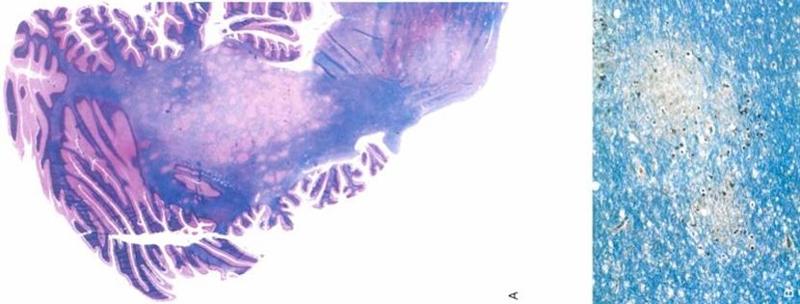

what is shown here

gliosis

what is this

myelin/fat stain of PML: large area in middle with no myelin